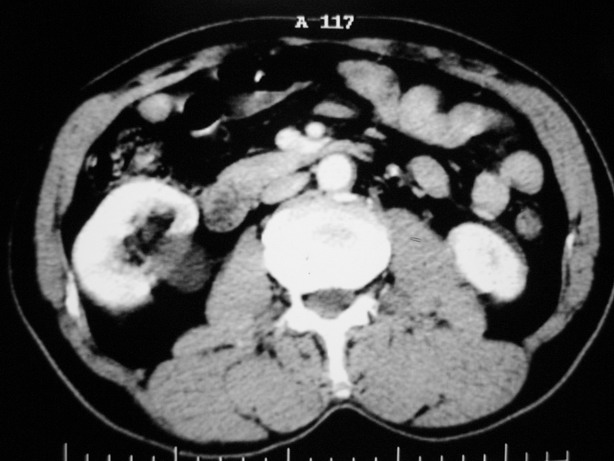

延迟期造影剂没有进入囊性病灶内考虑多发性肾囊肿,包括一个盂旁囊肿。

肾盂旁多囊性占位,有实性成分,增强有轻度强化,收集期病变内无造影剂显影。诊断肾盂旁囊肿,有实性成分无法解释,查书后诊断为:多房性囊性肾瘤!!不知大家同意否?????????对本病知道不多,望大家不吝赐教!!

囊间间隔强化与肾实质相仿,还是支持多发囊肿,定期复查

支持多发囊肿(所谓实质部分其实是肾实质)

右肾多发囊性低密度影,囊内有增强的隔及实性组织,考虑囊性肾癌。